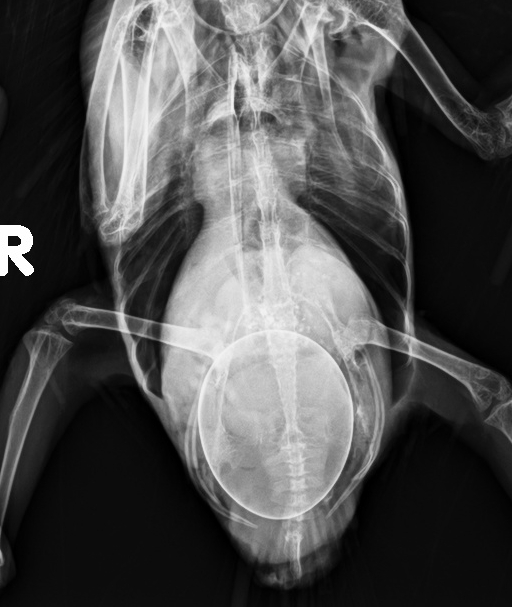

影像科